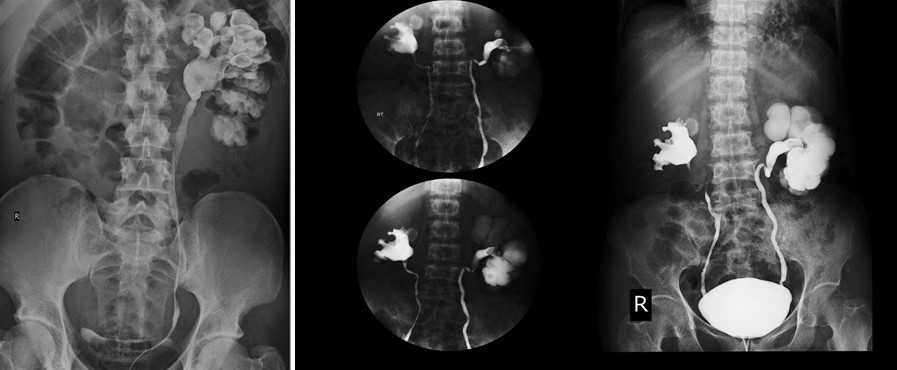

Экскреторная урография при нефроптозе: диагностические изображения